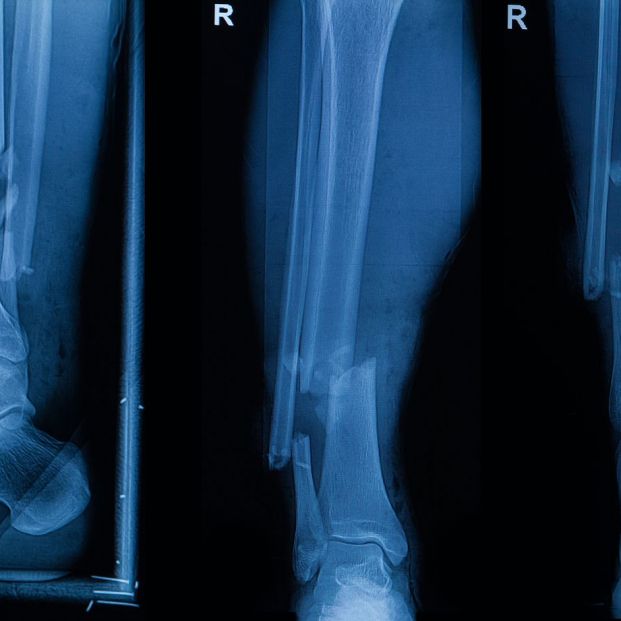

Probado en 150 pacientes

El valor clínico de Bone 02 ya se ha verificado en más de 150 casos de prueba en centros médicos de todo el país. En un caso, un joven trabajador sufrió una fractura conminuta del radio distal a causa de un traumatismo. Tradicionalmente, el tratamiento requería una gran incisión para implantar placas y tornillos, lo que causaba un traumatismo significativo, conllevaba riesgo de adherencia tendinosa o daño nervioso, y requería una segunda cirugía para su extracción.

Utilizando la tecnología adhesiva Bone 02, el equipo completó la adhesión y fijación precisa de los fragmentos óseos en tan solo 3 minutos mediante una incisión mínimamente invasiva de 2-3 cm, simplemente inyectando el material adhesivo. El seguimiento a los tres meses mostró una excelente cicatrización sin complicaciones, con la recuperación completa de la función de la muñeca.